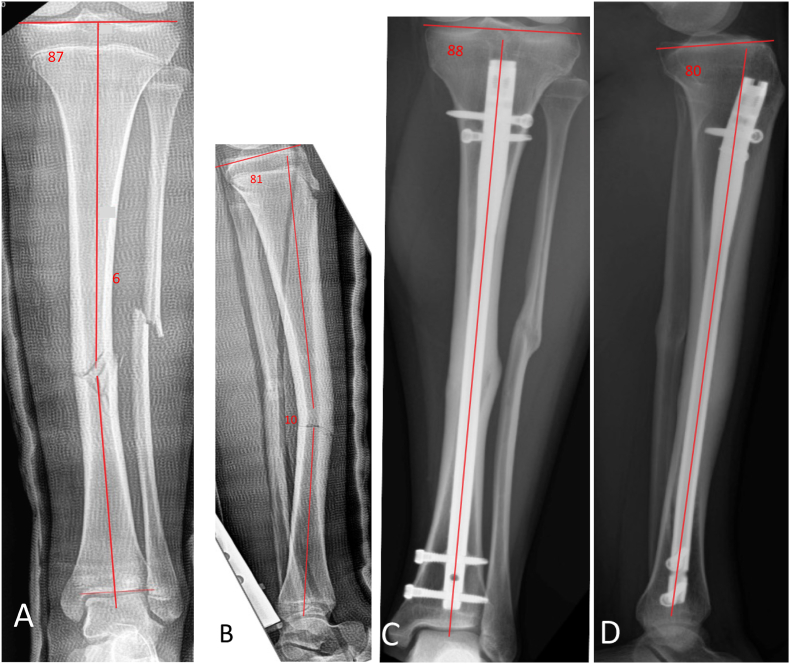

Methods: This single-center, retrospective cohort study analyzed patients aged 11-16 with open proximal tibia physis and tibial shaft fractures treated with IMN via the suprapatellar approach from January 2016 to October 2023. Demographic, fracture, and operative data were collected, and proximal tibial angles were measured. Follow-up radiographs were evaluated for tibial growth and alignment, with malunion defined as over 5 degrees of angular deformity.

Results: Thirty-five patients aged 11 to 16 (mean 14.7 years, SD 1.1) met the inclusion criteria. Males comprised 60%; the average follow-up was 12.4 months. Most fractures (74%, 26/35) were closed. The most common (57%) fracture pattern was OA42A1-3. Fracture union occurred by 9 weeks in 79% of cases. The mechanical Medial Proximal Tibial Angle (mMPTA, range 85-90 degrees) and Posterior Proximal Tibial Angle (PPTA, range 77-84 degrees) were normal in all pre-operative patients; there were no statistically significant changes in mMPTA and PPTA over the follow-up period. The reported Visual Analog Scale pain scale averaged 1.87 at the final follow-up. Most patients reported return to full activities (87%), with the operative leg comparable to the contralateral leg in 78% of cases.